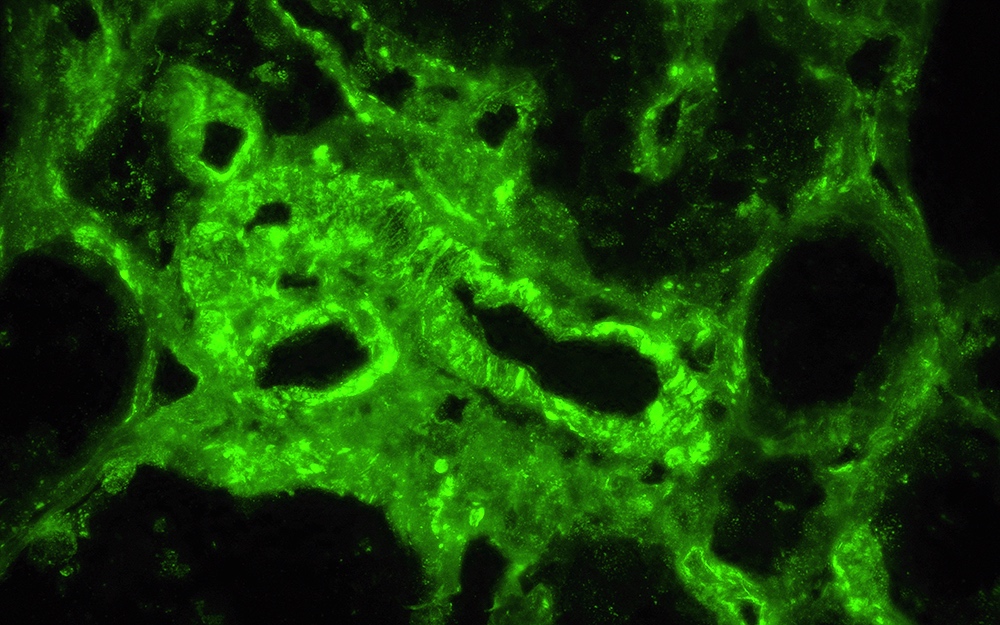

Immunofluorescence description

- Diagnostic criteria: IgG dominant full house immunofluorescence (positive IgG, IgA, IgM, C3, C1q, kappa and lambda light chains)

- Especially important are C1q positivity and extraglomerular immunostaining on the Bowman capsules, arteries, tubular basement membranes and in the interstitium

- Immunofluorescence staining is granular and may be subepithelial, intramembranous, subendothelial or mesangial

- In some cases, antinuclear antibody (ANA) test is seen with antibodies to IgG and the light chains

- Reference: Clin J Am Soc Nephrol 2019;14:1605

Immunofluorescence images

- Immunofluorescence microscopy: Up to 5 nonsclerosed glomeruli are available for evaluation. Mild to high intensity granular immunofluorescence staining was detected in the mesangial areas and less in the capillary walls with antibodies to IgG (4+), IgA (3+), IgM (2+), C3 (4+), C1q (3+), kappa light chains (4+) and lambda light chains (4+). Extraglomerular staining is seen on the arterial walls with antibodies to IgG.